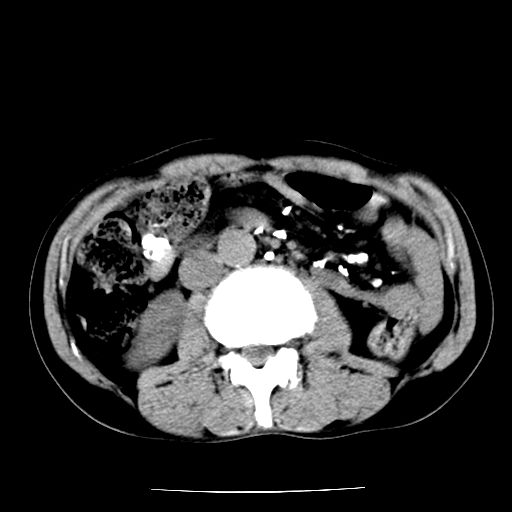

男,59岁,“结核性胸膜炎”30余年,胸部经常疼痛,多次x检查提示“肺部”炎症。腹部疼痛5日,b超提示:“肝内短管结石,余显示不清,建议进一步检查。”

两肺结核并右侧胸腔积液;脾脏、腹腔及腹膜后淋巴结结核[陈旧性];肝内胆管结石

胸部腹部都是结核(双肺。纵隔淋巴结,肝脏,脾脏,肠系膜)

两肺结核并右侧胸腔积液;脾脏、腹腔及腹膜后淋巴结结核[陈旧性];肝内胆管结石。直肠息肉?